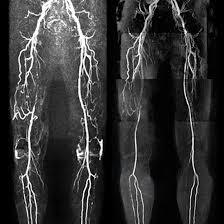

Looking for MR Angiography of Lower Limbs, Medifyhome assists you getting the best quality services of MR Angiography of Lower Limbs. Medifyhome incorporates Lower Limb MR Angiography, within its advanced diagnostic services, and clinical practice. This non-invasive imaging test helps obtain images of blood vessels in the legs and it is possible to find blockage, narrowing, or other such problems in the leg arteries and veins. Medifyhome makes the best care of its patients by collaborating with the most reliable diagnostic centers which perform comprehensive and accurate procedures of Magnetic Resonance Angiography (MRA). The test employs the use of magnetic resonance technology and sometimes the use of contrast medium to highlight areas of blood vessels to aid in the diagnosis of conditions such as peripheral artery disease or evaluation of blood vessels after a trauma. Medifyhome is a good option for any medical diagnostics because the patients are treated by skilled professionals using the latest equipment and all diagnostics procedures are performed very quickly. Book an appointment at Medifyhome for MR Angiography Lower Limbs at a reasonable price, or call our custom care at +919100907036, +919100907622.